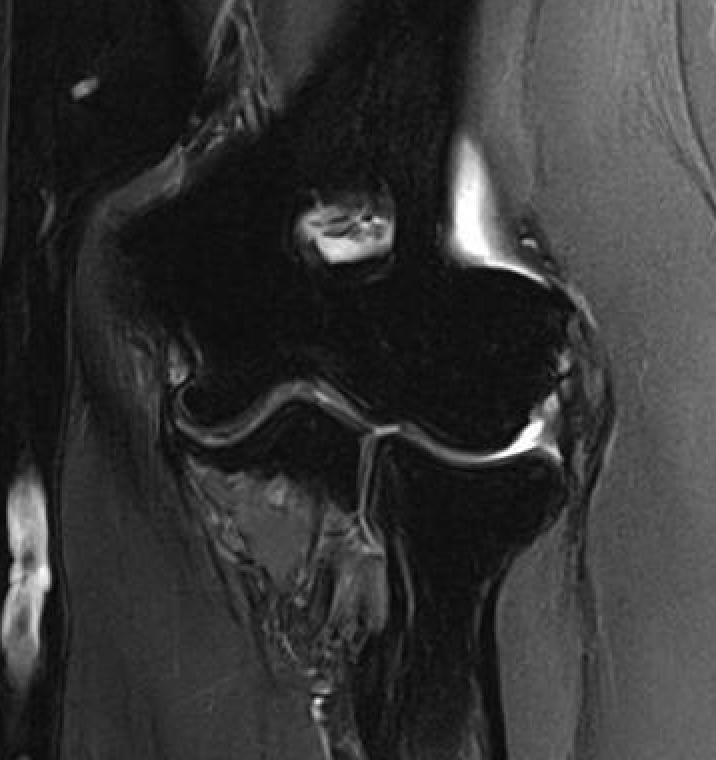

MRI

High grade partial tears of ECRB on lateral eipcondyle

Tendonopathy of the common extensor origin, with thickening and high grade tear partial tear